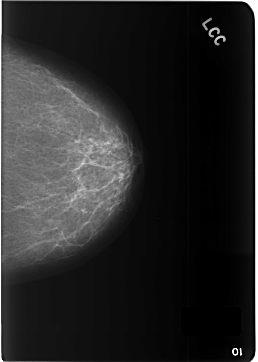

C_0342_1.LEFT_CC

LEFT_CC LINES 5784 PIXELS_PER_LINE 4120 BITS_PER_PIXEL 12 RESOLUTION 50 NON_OVERLAY